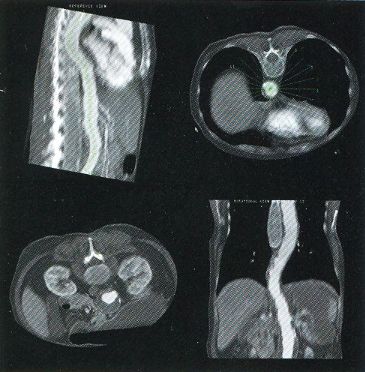

The first workstation to be seriously marketed was Voxelscope II (VS2) which had greatly enhanced volume memory and higher display resolution. Unfortunately, that came at a cost and it, and all its successors never even came close to achieving the true video-rate real-time performance of the VPP, which would have required the massively parallel technology in the Patent. But even very early on, VS2 had somewhat real software with a Graphical User Interface (GUI) and enough functions to be credible, at least for demos including instantaneous Multi-Planar Reformatting (MPR) which could display a slice though the object at any depth aligned with one of the principal axes (axial, saggital, or coronal) or at an arbitrary angle, as well as real-time (fraction of a second, but not video rate) 3-D shaded surface with density selection and slicing. A Motorola 68000-based VME bus single board computer replaced the PDP-11 or VAX (sorry DEC) and implemented the high level control and Graphical User Interface (GUI), ran the file system, and interfaced to the outside world.

These photos of the Voxelscope II screen are typical of the types of rendering provided by the system.

Voxelscope II Screen Shots. Combination of 3-D Shaded Surface, Multiplanar Reformatting, and Segmentation

Of course, once there was a real Marketing department, the real Software types (led by Eddie Wyatt) were always slowing things down anyhow in the interest of generality - or to concentrate on features users might actually care about! What a conecpt? ;-) One example was Multi-Planar Reformatting or MPR where a single cut along one of the principal planes - axial (XY), saggital (YZ), coronal (XZ) - or at an arbitrary angle or even curved cut through the object is displayed. MPR could have run at full video rates on any of the machines, but no matter how hard I tried to convince Software to improve the performance, it never chugged along at more than a couple frames per second. :( :) And large portion of the VS2 hardware capabilities were never exploited due to feature priority as determined by Marketing.